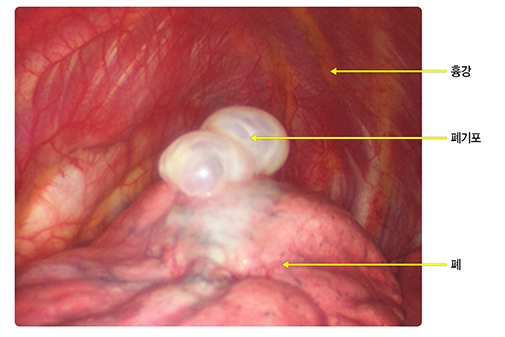

일차성 자연기흉은 질병이 없는 10대부터 30대의 키가 크고 마른 남자에서 잘 발생합니다. 폐의 표면에 풍선처럼 부푼 폐기포가 저절로 터지면서 구멍이 생겨 들이마신 공기가 흉강으로 새어 나가 발생합니다. 폐기포가 생기는 원인에 대해서는 아직 완벽하게 밝혀지지 않았습니다. 성장 과정에서 폐의 윗부분이 폐혈관의 성장에 비해 더 빠르게 성장하면서 혈액공급이 부족해져서 발생한다거나 폐 윗부분의 폐포 내부 압력이 상대적으로 높기 때문에 발생한다고 추정하고 있습니다

흉부 컴퓨터단층촬영(Computed Tomography, CT)은 통상적으로 기흉 자체를 진단하기 위해 시행하지는 않습니다. 수술 치료가 필요한 환자에서 기흉의 원인이 되는 폐기포의 위치와 크기를 평가하거나 동반된 다른 질환의 여부를 확인하기 위해 사용됩니다.

기흉에 대한 수술 치료는 폐기포 절제술과 기계적 흉막유착술로 구성되어 있습니다. 과거에는 가슴을 절개하고 들어가 폐기포를 잘라내고 손으로 직접 봉합했으나 근래에는 흉강경 및 자동봉합기 등의 발전으로 1~2 cm 미만의 작은 상처를 통해 시행하는 비디오 흉강경수술이 주로 사용되고 있습니다. 비디오 흉강경수술은 흉터가 작고, 수술 후 통증이 적으며 환자의 회복 기간도 빠르다는 장점이 있습니다.